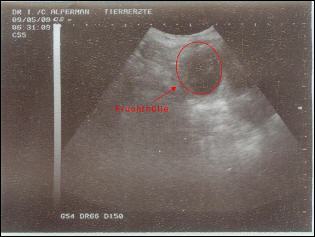

Wir waren mit Pepsi zum Ultraschall !

Pepsi fährt zum Ultraschall (09.Mai 2009)

Irre wie schnell doch die ersten vier Wochen seit dem Decken vergangen sind.

Heute sollte die Ultraschalluntersuchung zeigen, ob sich das Daumendrücken gelohnt hat und Pepsi tragend ist.

Unsere Freude war natürlich riesengroß, als wir auf dem Ultraschall sehen konnten, dass Pepsi um den 11. Juni 2009 Babys (Stichtag) bekommen wird.

Wir erwarten in diesem Wurf schwarze und gelbe Welpen.

Jetzt freuen wir uns auf eine schöne Zeit und sind schon ganz gespannt auf die kleinen Hundebabys. |